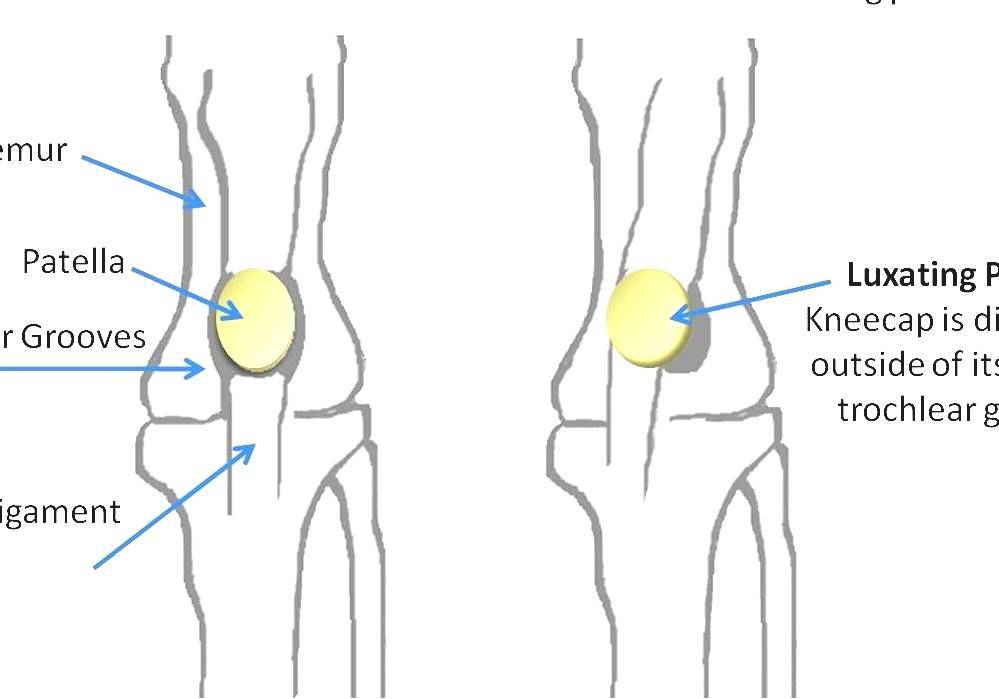

Apex patellae

Apex patellae 117 фото